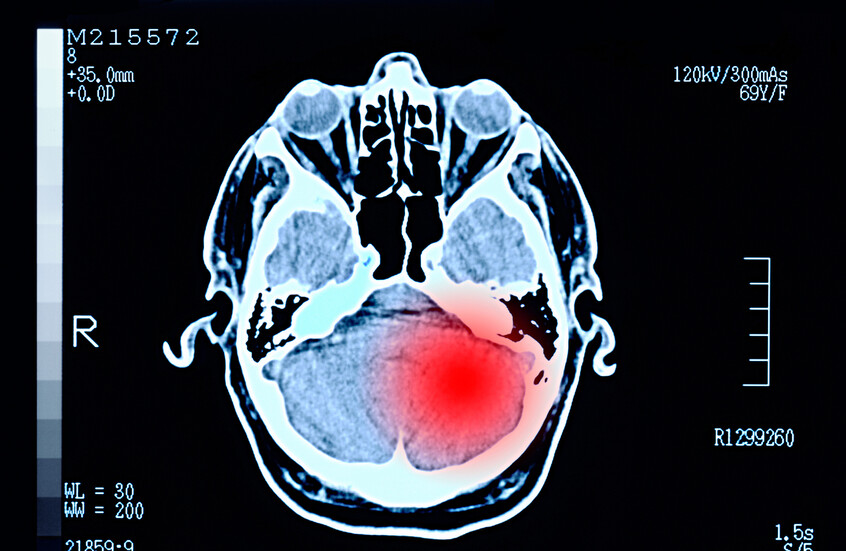

دراسة تكشف "نقطة ضعف خفية" في أخطر أورام الدماغ

حدد فريق دولي من العلماء "نقطة ضعف خفية" في دفاعات أحد أكثر أشكال سرطان الدماغ عدوانية، ما يشير إلى أن نظاما غذائيا متخصصا يمكن أن يلعب دورا حاسما في إبطاء نمو الورم.

وتوصل فريق من العلماء من خمس دول أوروبية، في دراسة نشرت بمجلة Science Advances، إلى أن الأدوية الشائعة من عائلة الستيرويد، والمستخدمة غالبا لعلاج الالتهاب المرافق للورم الأرومي الدبقي في الدماغ، تقوم بعمل مزدوج.

فهذه الأدوية لا تقلل الالتهاب فحسب، بل تعيد برمجة عملية التمثيل الغذائي للخلايا السرطانية بشكل جذري، وتحديدا في طريقة تعاملها مع فيتامين B3.

وهذا التغيير الاستقلابي، كما وصفه العلماء، يكشف عن "نقطة ضعف خفية" في بنية الورم. والأهم من ذلك، أن هذه الثغرة قابلة للاستغلال العلاجي، حيث وجد العلماء أن حرمان الخلايا السرطانية من حمض أميني محدد يسمى "الميثيونين" – عن طريق وضع المريض على نظام غذائي معد خصيصا يكون منخفضا جدا في هذا الحمض – يؤدي إلى تجويعها فعليا.

فبعد أن غيرت أدوية الستيرويد سلوكها، تصبح الخلايا السرطانية في أمس الحاجة إلى مشتقات هذا الحمض الأميني لمواصلة النمو والانتشار.

وبهذا، يطرح البحث استراتيجية علاجية جديدة تعتمد على التآزر بين دواء قديم ونهج غذائي مبتكر. فبدلا من الاعتماد على الدواء وحده، يتم الجمع بينه وبين تقييد غذائي محسوب، لخلق حالة من الحصار المضاعف على الورم.

ويأتي هذا الاكتشاف كنبأ سار في معركة طبية صعبة، إذ يتميز الورم الأرومي الدبقي بنموه السريع ومقاومته الشديدة للعلاجات التقليدية. وقد أعرب الخبراء عن تفاؤل حذر، مشيرين إلى أن مثل هذه الاكتشافات التي توفر أملا في إبطاء زحف الورم وتمنح المرضى وعائلاتهم وقتا ثمينا، هي بالضبط ما يحتاجه المجال الطبي.

وتتمثل الخطوة الحاسمة القادمة في نقل هذه النتائج الواعدة من أروقة المختبرات إلى أسرة المرضى، عبر تجارب سريرية دقيقة تختبر فعالية وأمان هذه المقاربة العلاجية الجديدة.